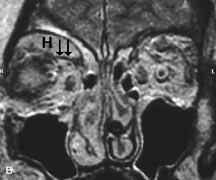

Lymphomas have MRI characteristics similar to those of inflammatory lesions in that they are hypointense to fat and isointense to muscle on T1-weighted images (Fig. 22). They may appear hyperintense to fat on T2-weighted images, perhaps owing to less fibrosis than that seen in orbital inflammatory pseudotumor, although this is not a consistent finding.31,50,66 Lymphoid tumors typically enhance moderately after contrast injection. Unfortunately, studies have shown that tumor density and homogeneity are similar between inflammatory and malignant orbital infiltrates, and MRI cannot differentiate these lesions.72,73

Fig. 22. A and B. T1- and (C) T2-weighted MR scans demonstrate a poorly defined multicompartmental mass enveloping the lateral rectus, superior rectus, and levator palpebrac superioris muscles. The lesion is isointense to brain on T1- and T2-weighted scans, as is typical for highly cellular neoplasms. D. Postcontrast fat-suppressed T1-weighted scan demonstrates intense enhancement of the infiltrating intraconal and extraconal tumor.